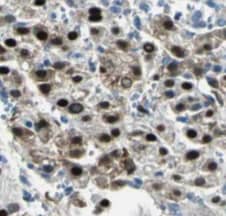

Applications: WB, IHC

Applications: WB, ELISA, ICC/IF, IHC, IP